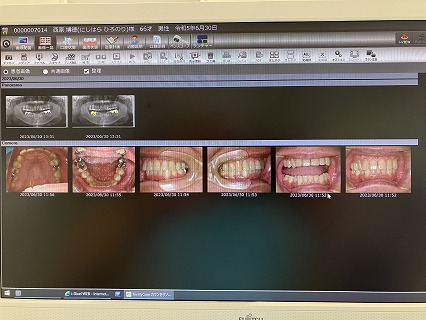

2024年7月5日(金) 右上奥歯の虫歯が痛んだ

2024年6月7日(金) 銀冠

23.7.21 検査 PDF

23.10.27 検査 PDF